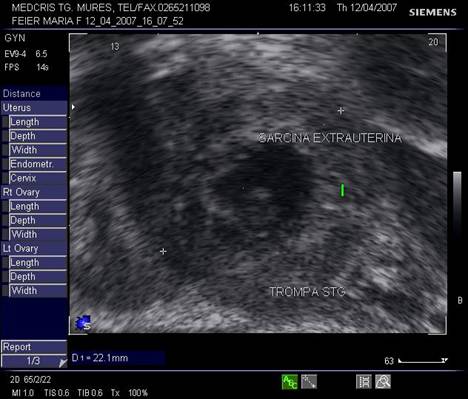

Fig nr 62 Sectiune transversala la nivel corpului uterin , la ecografia transvaginala. Parauterin, in trompa stg., se evidentiaza o formatiune inomogena cu ecou hipoecogen relativ central

clinic are semne de abdomen acut si mult lichid liber anecogen in fundul de sac Douglas.

Daca sangerarea este proaspata, retrouterin apare doar o zona hipoecogena, eventual cu fine ecouri interne. Daca ruptura este mai veche, cu organizarea unui hematom, apar si zone hiperecogene si inomogene. Cand hemoragia interna este mai mare, ecografia abdominala va evidentia lichid liber si paraombilical sau supraombilical.